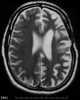

Rasmussen syndrome type 2